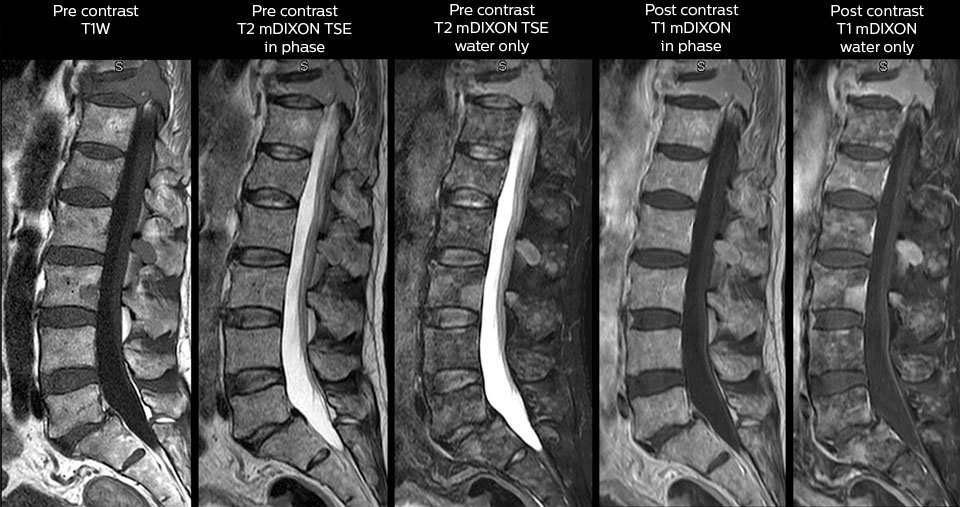

To minimize the time taken to perform scans, rapid MRI examination protocols (ExamCards) were developed, shortening the total scanning time to even less than 10 minutes in some exams. Techniques like mDIXON (modified DIXON) are used for robust capturing of fat-free MRI images in a hectic ED environment.

in image acquisition and postprocessing algorithms.”“mDIXON TSE sequences allow simultaneous characterization of morphological changes from the in-phase T2-weighted images and visualization of edematous changes, thanks to the water T2-weighted images from the same acquisition. Anatomical and morphological considerations could be a partial or complete ligament tear, a bony avulsion or hematoma.”

“mDIXON TSE sequences allow simultaneous characterization of morphological changes from the in-phase T2-weighted images and visualization of edematous changes, thanks to the water T2-weighted images from the same acquisition. Anatomical and morphological considerations could be a partial or complete ligament tear, a bony avulsion or hematoma.”

“We use mDIXON TSE extensively in our spine imaging in the emergency room,” says Dr. Karis. “It’s particularly nice in that it is very robust with regard to susceptibility type of problems that would come up with traditional spectral fat-saturated images; these problems are essentially eliminated with the mDIXON technique. In our ED environment it’s really nice to have the fat-free imaging that goes along with the mDIXON technique.

“For the thoracic and cervical spine routine non-contrast exam, for example, we perform one mDIXON T2 TSE sequence, which provides us with two outputs: the fat-and-water-together T2-weighted images, as well as the water-only sagittal T2-weighted images. And then we also perform an axial gradient echo exam.”